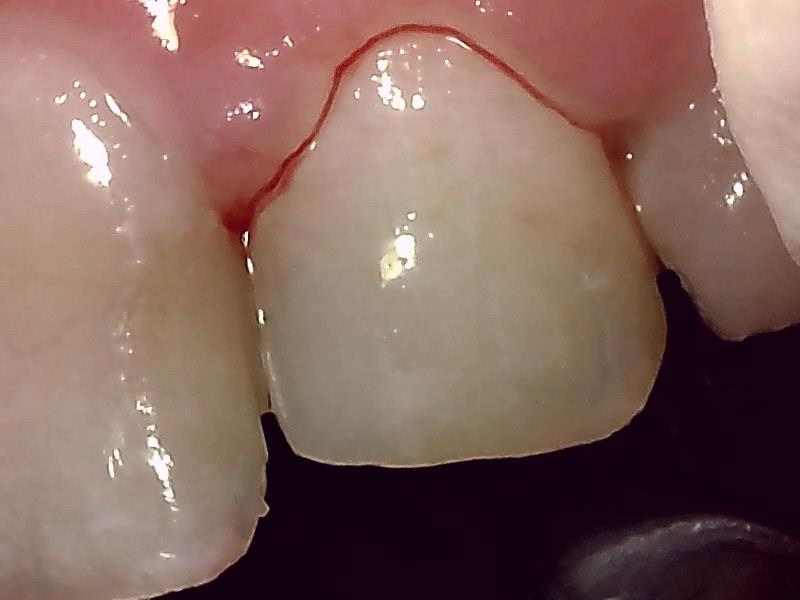

保険レジン充填の症例(前歯)

Before

After

| 主訴 | 前歯が欠けてしまい、見た目が気になる |

|---|---|

| 年齢・性別 | 20代 男性 |

| 治療方法 | コンポジットレジン充填 |

| 費用 | 保険診療 |

| デメリット・注意点 | 金属(メタル)やセラミックと比較すると強度が低いため、硬いものを噛んだり、強い衝撃が加わると再破折するリスクがあります。 |